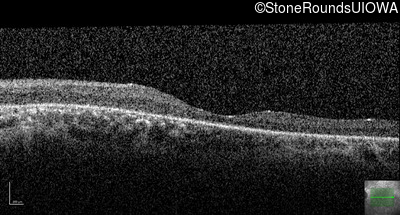

Optical Coherence Tomography - Right - 20/100

Exemplar / OCT Stack